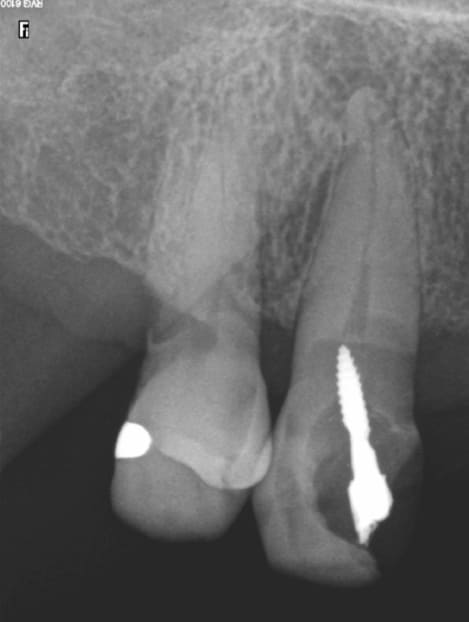

docgentil

04/05/2016 à 18h13

Le Screw du jour.

Ce qui m'attriste le plus c'est que le patient a 25 ans.

Sc33 bczylk - Eugenol